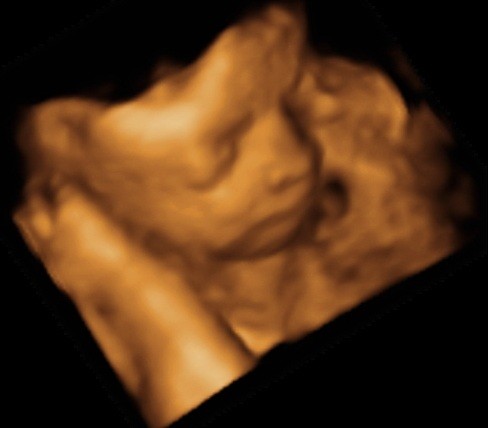

ślicznyNie wiem, ktory temat odpowiedni, wiec wstawie fotki naszego synka tutaj (nie sa to medyczne skany, wiec watek lekarski chyba nie pasuje, nie sa to tez zdjecia brzuszka...)

Zobacz załącznik 435455

Zobacz załącznik 435456

Zobacz załącznik 435457

Zobacz załącznik 435458

Zobacz załącznik 435459

Powiedzcie do ktorego tyg ciazy mozna robic usg 3D?